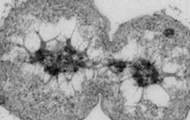

Он уникально взаимодействует с типами азота и азотным циклом и живет с типом бактериофага.